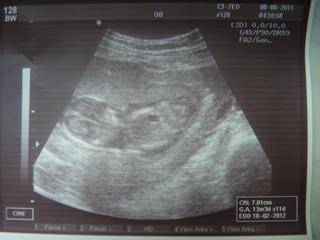

Moje mimi mělo teraz 5,7 cm (po zadeček) - což prý odpovídá 12+2 (a byla jsem podle MS 11+4) Takže je o drobec větší...Ale počítá se velikost dle ultrazvuku - tedy 12+2 týden